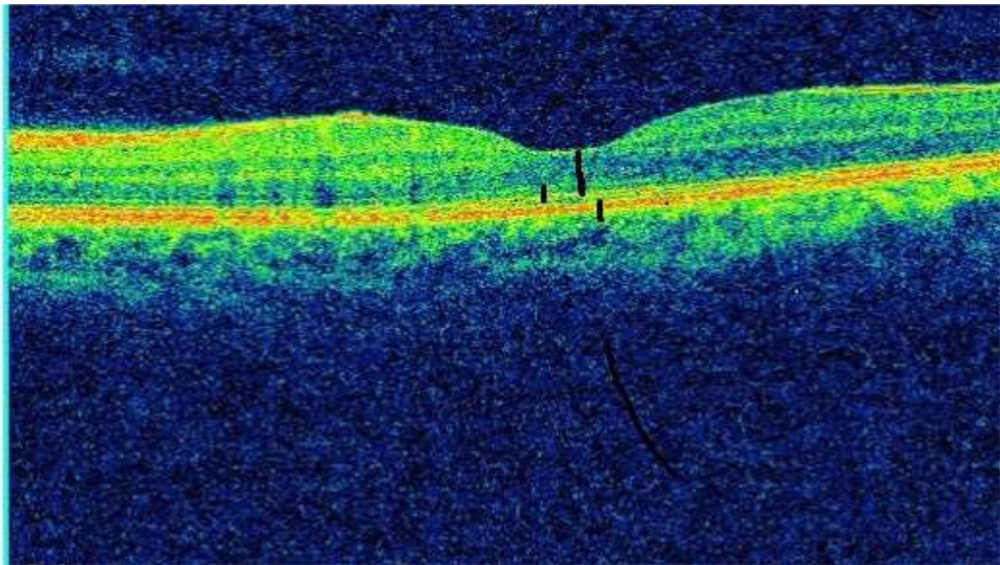

The retinal thicknesses were measured by experienced observer who was masked to the diagnosis and other clinical information. They measured the retinal thickness manually with the embedded OCT software. The ONL thickness was distance between the outer border of the inner limiting membrane and external limiting membrane (ELM) at fovea. The photoreceptor IS length was measured as distance between ELM and outer border of highly reflective line representing the ellipsoid zone (EZ) at the central fovea. The photoreceptor OS length was measured as distance between EZ and RPE at the centre of fovea. (Fig.2)

Fig-2 ONL, IS, OS thickness at fovea.